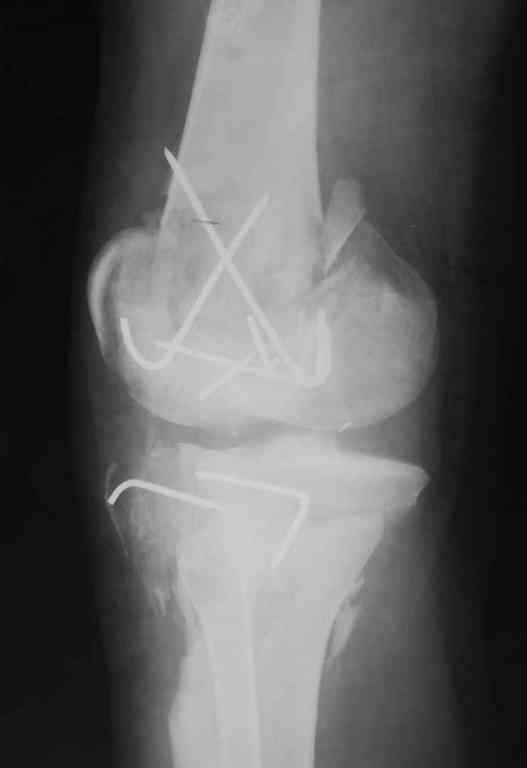

[Ortho] Последствия открытого перелома дистального отдела бедра

Вложение не в текстовом формате было извлечено…

Имя     : 2.jpg

Тип     : image/jpeg

Размер  : 73071 байтов

Url     : http://weborto.net:8080/pipermail/ortho/attachments/20100908/be90ac55/attachment-0003.jpg